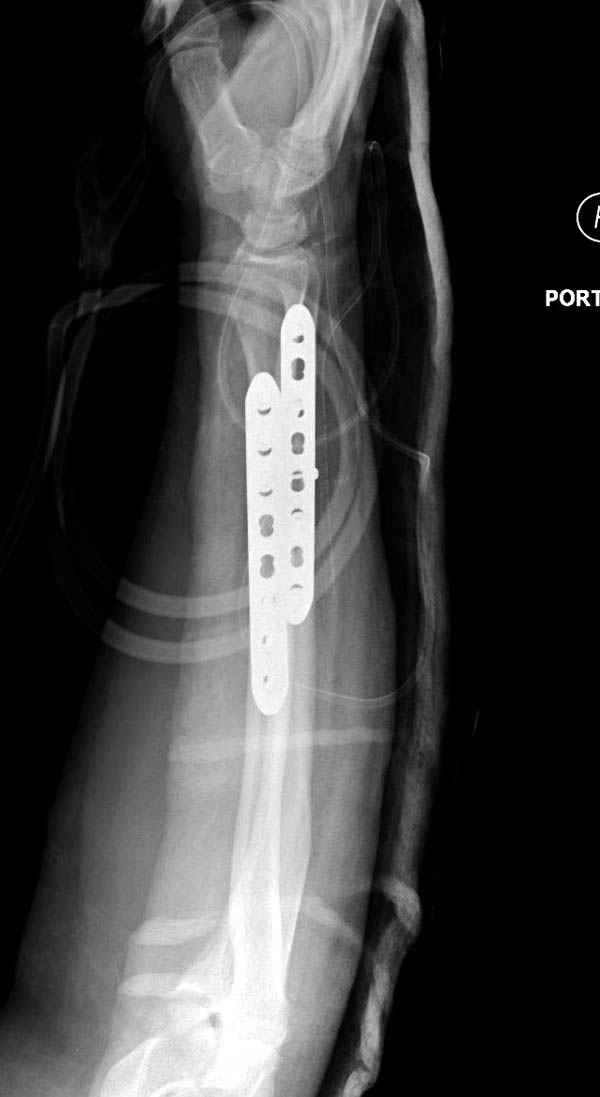

Второй случай, для лечения перелома проксимального

плеча применили пластину "Hand Innovation"

http://www.handinnovations.com/pdf/S3_technique.pdf

Пластина имеет преимущества перед другими "Locking

Implants", потому что пластину можно уложить намного ниже чем другие пластины и имеется возможности проведения шурупов под 130 градусным углом, таким образом можно уменьшить операционный разрез в проксимальной части.

Прооперирован вчера на 13 день после поступления.

На 20-е сутки снял гипс, одел фиксирующюю

ортопедическую повязку. Вот контроль. Как видно, стояние хорошее, уже формируется костный мозоль.

Думаю еще недели 3 продолжать фиксацию.

Из-за большого обьема конечности доступ к бугорку был затруднен, предварительно зафиксированный шуруп не удержал бугорок, поэтому фиксацию провели толстыми нитками. Состоятельность фиксации бугорка обычно проверяем во время операции, под рентген контролем проводится движения конечности, особенно приведение.